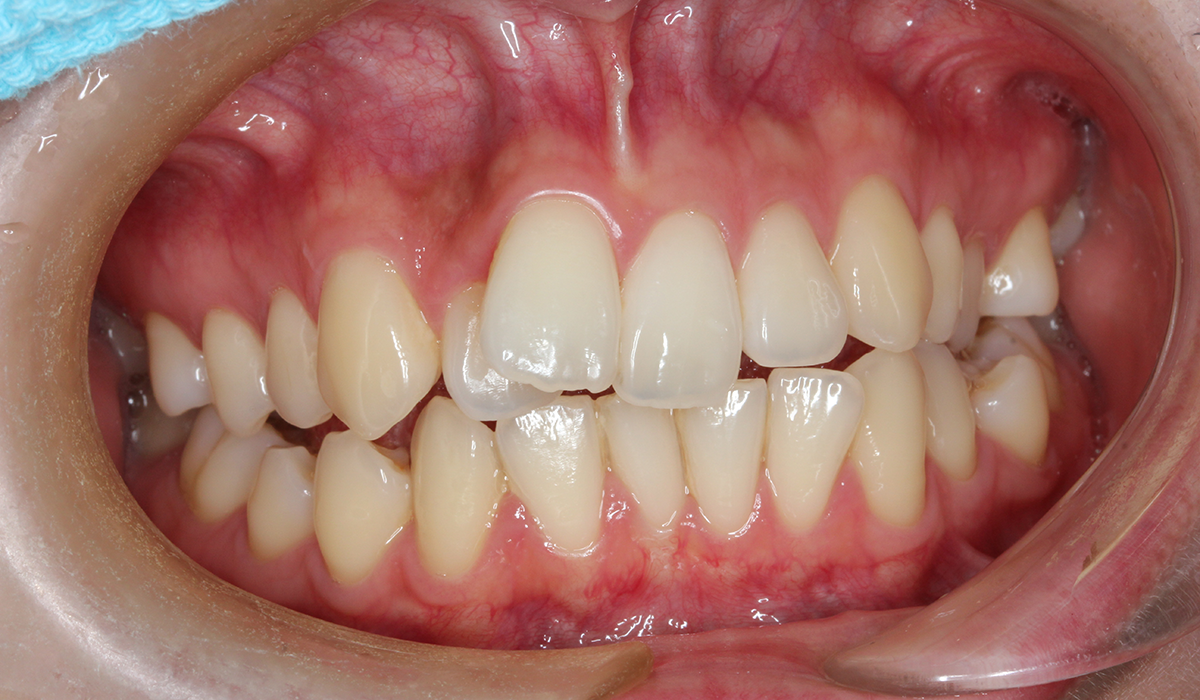

今回ご紹介する患者様は、全体的な歯のガタツキを気にされており、矯正検査後叢生Ⅰ級と診断いたしました。

正面

術前

右側

左側